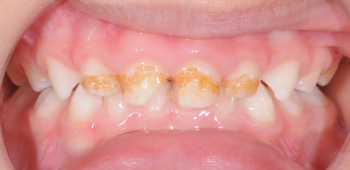

Odontopediatría

Caso 1